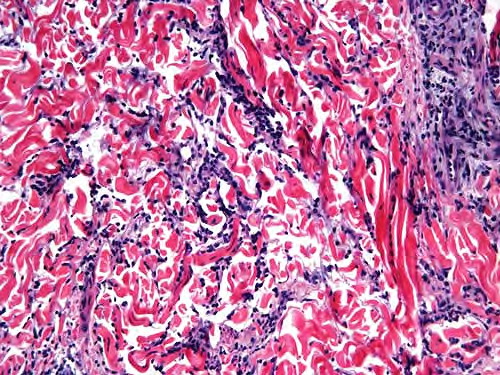

Interstitial granulomatous dermatitis = التهاب الجلد الحبيبومي الخلالي